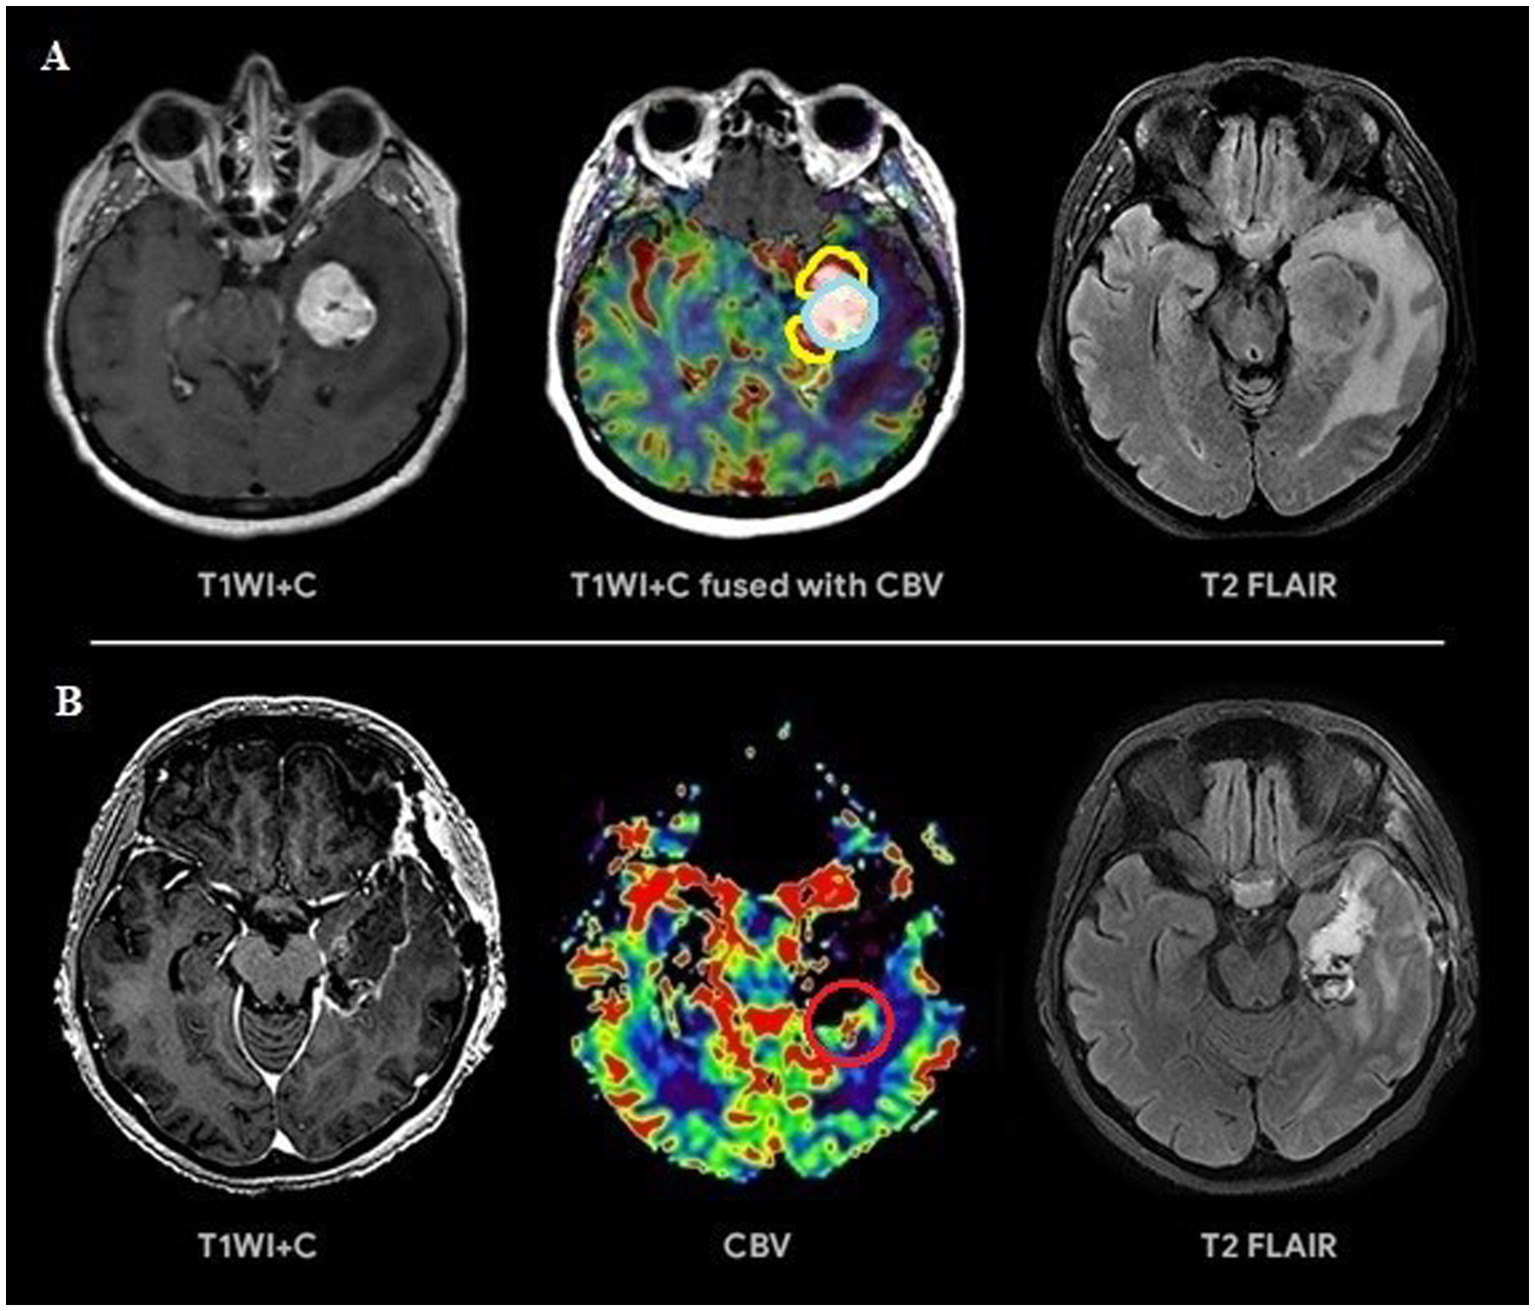

Figure 4

(A) Preoperative tumor resection planning in 52-year-old patient with left temporal lobe glioblastoma with regard to comparison of postcontrast T1 series, CBV parameter obtained using DSC-T2* perfusion and T2-Flair. The tumor compounds of 2 portions: contrast-accumulating (blue line) and contrast-negative with high CBV level (yellow line). (B) Postoperative MRI control 24 h after operation, post-contrast T1 series, CBV indicator obtained using DSC-T2* perfusion and T2-Flair. MRI data indicating resection of the contrast-enhancing tumor part and with residual hyperperfused fragment at the lower pole of resection zone (red circle).